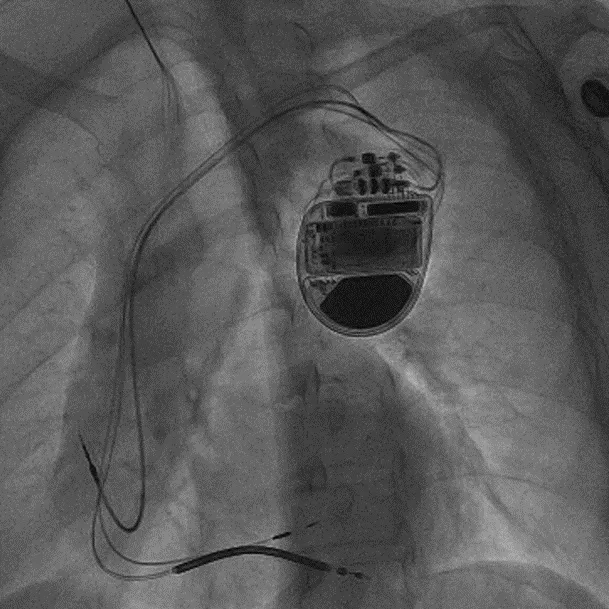

拔除无导线起搏器后植入左束支CRTD的术后影像

术前,汤宝鹏教授带领治疗团队对文献进行了详细查阅,对病情进行了充分而细致地评估,对术中可能出现的各种风险做好了各项应急预案。术中,手术团队使用圈套器成功抓捕无导线起搏器Micra尾端并顺利拔除,同时给患者植入左束支心脏再同步起搏除颤器。手术顺利,患者术后恢复良好。